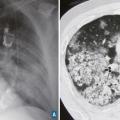

L’atteinte pulmonaire est variable : infiltrats alvéolaires, aspect en verre dépoli, nodules multiples excavés (fig. 9). L’hémorragie alvéolaire, complication majeure mais rare de la granulomatose avec polyangéite, se produit au niveau de la circulation pulmonaire distale entraînant un comblement alvéolaire (fig. 10). Elle se manifeste par une hémoptysie, une dyspnée, une anémie, des opacités diffuses alvéolaires et un liquide hémorragique au lavage bronchoalvéolaire (LBA). Des sténoses trachéo­bronchiques sont possibles.